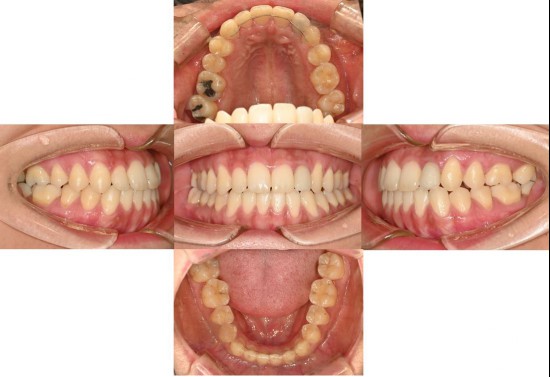

Dentists around the world must recognize that treating patients based on the conventional habitual jaw position can significantly impact their lives.

Not long ago, a practicing physician from Prague visited my clinic during orthodontic bracket treatment. She was diagnosed with facial asymmetry and body misalignment, and experienced MCB splint therapy. She was aware that bodily misalignment is related to asymmetry in the facial bones.

Yesterday, a person from Canada came in; this individual had undergone extraction orthodontics and whom I had consulted with online three years ago.